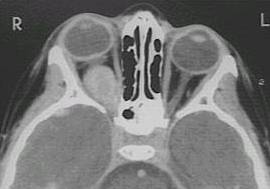

What type of image is it? CT scans or MRI scans (T1 or T2

weighted)

Which plane the image is in? axial, sagittal or coronal.

brain lesion (enlarged pituiary fossa suggests

pituitary tumour, wedge-shaped hypodense area suggests cerebral ischamia;

wedge-shaped hypodense area suggests cerebral haemorrahge)?

Click the following pictures for Questions

and Answers.